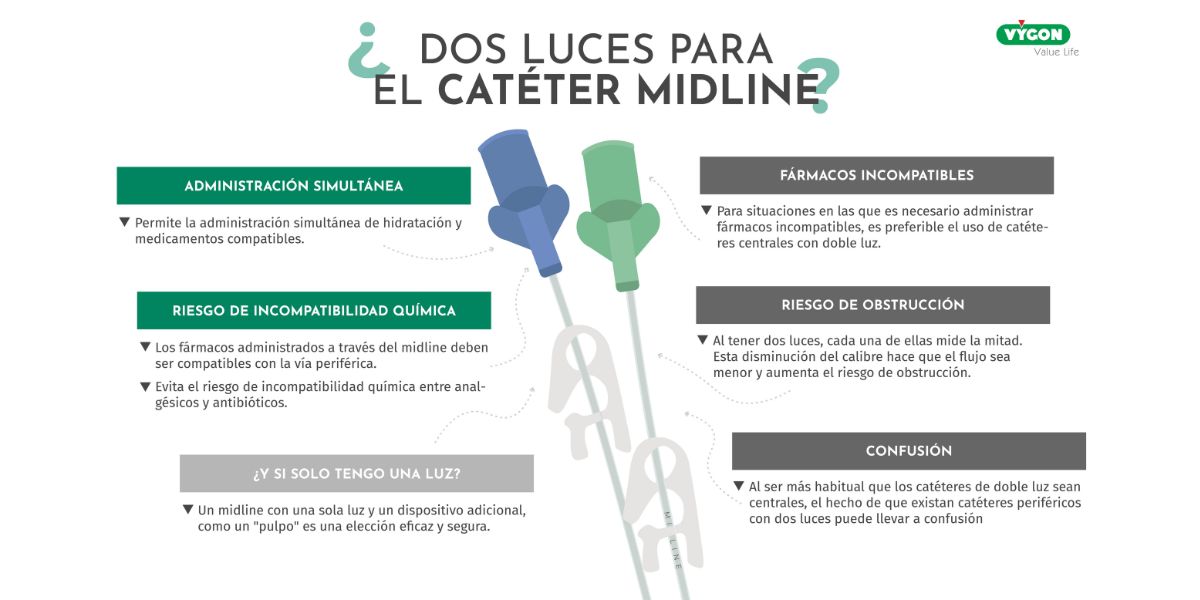

Doble luz en el catéter Midline

Catéter Midline de dos luces: permite administración simultánea de medicamentos compatibles, reduce riesgo de incompatibilidad química y obstrucción..